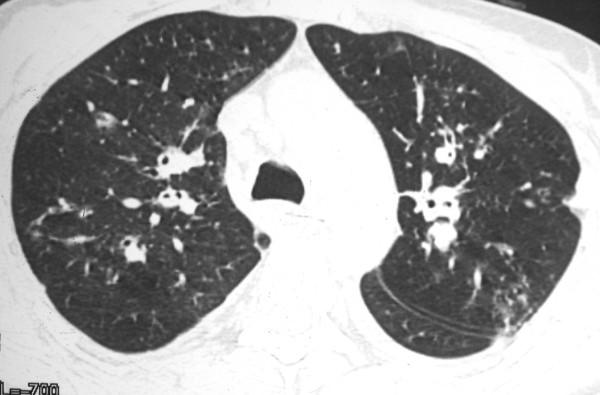

Approximately 90% to 95% of Kaposi sarcoma cases occur in human immunodeficiency virus - infected homosexual and bisexual men. Pulmonary Kaposi sarcoma is uncommon in women, and rarely considered as a potential cause of diffuse lung disease in women with acquired immunodeficiency syndrome. The disease is usually mistaken clinically for pulmonary infection. A 32-year-old woman was admitted with a 2-month history of dyspnea, evening fever, hemoptysis, weight loss, and generalized adenomegaly. Physical examination showed erythematous macules in the lower limbs. Skin and open lung biopsy demonstrated Kaposi sarcoma. Computerized tomography demonstrated peribronchovascular interstitial thickening. Although uncommon, pulmonary Kaposi sarcoma should be considered in the differential diagnosis of diffuse lung disease in women with AIDS.

约90%至95%的卡波西肉瘤病例发生于感染人类免疫缺陷病毒的同性恋和双性恋男性。肺卡波西肉瘤在女性中并不常见,在获得性免疫缺陷综合征女性患者中很少被视为弥漫性肺病的潜在病因。临床上该病通常被误诊为肺部感染。一名32岁女性因2个月的呼吸困难、午后发热、咯血、体重减轻及全身淋巴结肿大入院。体格检查发现下肢有红斑。皮肤及开放性肺活检显示为卡波西肉瘤。计算机断层扫描显示支气管血管周围间质增厚。尽管罕见,但在艾滋病女性患者弥漫性肺病的鉴别诊断中应考虑肺卡波西肉瘤。